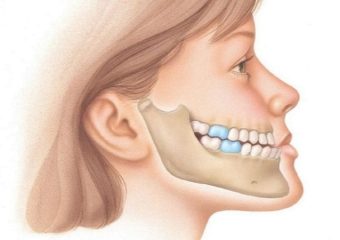

درمان جلو بودن دندان و فک پایین (آندربایت)

بررسی درمان جلو بودن دندان و فک پایین (آندربایت)

نیازی نیست که یک مشکل دندانپزشکی رایج مانند آندربایت مانع لبخند زدن شما شود. این در حالی است که تعدادی از آندربایتها مشکل ایجاد نمیکنند اما سایر آندربایتها ممکن است باعث ایجاد مشکلاتی در غذا خوردن، صحبت کردن، درد در فک، سردرد و اختلالات انسدادی در هنگام خواب شوند. درمان صحیح آندربایت به شرایط و سن بیمار بستگی دارد. اما این درمان همیشه مستلزم کمک یک دندانپزشک یا متخصص ارتودنسی است. در ادامه این مطلب سایت دکتر ندا مکانیک بهترین دندانپزشک زیبایی اصفهان درمان جلو بودن دندان و فک پایین را مورد بررسی قرار می دهیم.

تعریف آندربایت

آندربایت (underbite) شرایطی است که در آن دندانهای پایینی به سمت جلو میآیند. طوری که در ظاهر به نظر میرسد که فک از دهان بیرون زده است. مشکل آندربایت میتواند خفیف یا شدید باشد که مستلزم درمان دندانپزشکی است. این در حالی است که دندانهای پایینی که به سمت جلو هستند به ندرت خود به خود منظم میشوند. چون عوارض آندربایت شامل تنفس دهانی، مشکل در صحبت کردن و پوسیدگی دندان میشود. درمان اهمیت دارد.